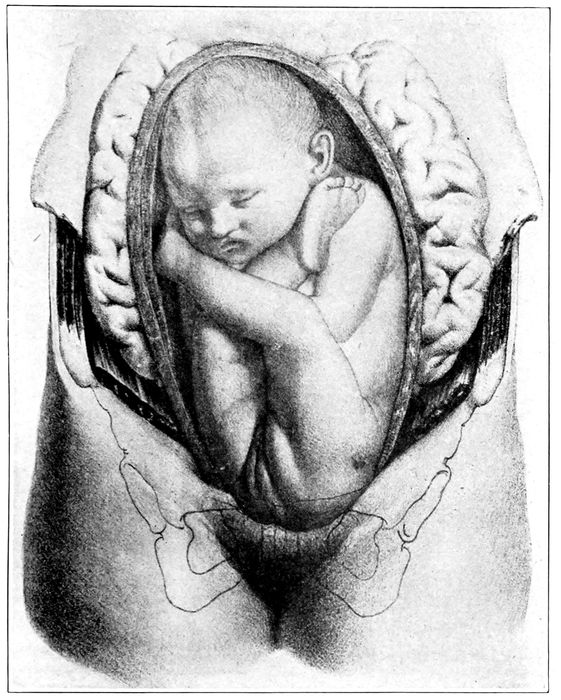

Child in second stage of labor |

116 |

| |